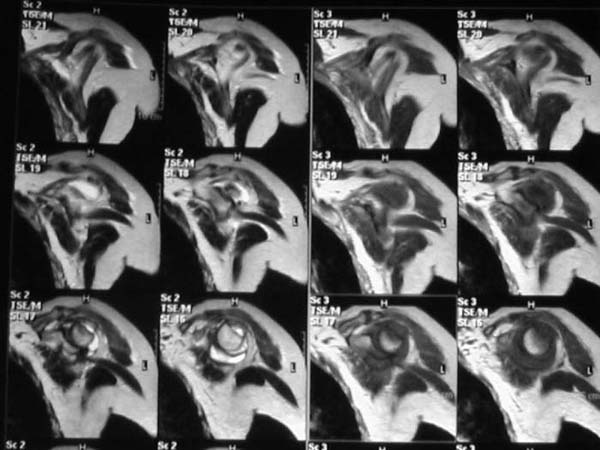

Уважаемые коллеги!Женщина, 60 лет. 3 недели назад упала с упором на отведенную левую руку. Почувствовала боль в левом плечевом суставе. За помощью не обращалась. 2 недели "мази и припарки". Затем - рентгенограмма (r1 и r2), жалобы на боли,ограничение движений...

Активное отведение 80 гр., при пальпации - головка плечевой кости безболезненно вправляется и тут же самостоятельно вывихивается. Наложена косыночная иммобилизация, рентгенография (r3) и МРТ.В нашем диагностическом центре МРТ исследование плечевого сустава выполнено впервые, опыта у нас маловато :(.Вопросы: уточнение диагноза? какие исследования провести? тактика лечения?

Из того, что видно на недостаточно качественно отсканированных МРТ - нижний подвывих плеча и синовиит. Непонятный очаг по заднему контуру головки плеча (то ли артефакт, то ли косой срез, проходящий между головкой и большим бугорком). Сухожилия вращательной манжетки выглядят целыми. Неправильная форма нижней части labrum glenoidale - разрыв ?

МРТ должен показать разрыв манжетки, но признаться я не большой эксперт по чтению МРТ сканов, хотя затемнение, отек мягких тканей по задней поверхности плеча видны Обычные рентгенограммы демонстрируют остеолизис в области большого бугорка.

1. На рентгене - нижний подвывих плеча и очаг остеолиза суставного бугорка с четкими контурами (вдавленный перелом на фоне остеопороза ? доброкачественная опухоль? аваскулярный некроз ? (хотя ни разу не слышал об аваскулярном некрозе плеча..)

Судя по снимкам, речь идTт о типичном случае Hill-Sachs Lesion. По этому поводу я позволю себе некоторый экскурс:

97 % всех вывихов плеча происходит по механизму комбинации отведения, разгибания и наружной ротации (А. Гринспан). В момент вывиха головка плеча ударяет о нижний край гленоида, что ведет к вдавленному или компрессионному перелому одной или обеих структур. Чаще всего, однако, повреждение возникает в задней латеральной области головки плечевой кости на переходе от головки к шейке. Этот диагноз можно выставить на основании рентгеновского снимка в переднезадней проекции с внутренней ротацией плеча. Несколько реже видно повреждение гленоида о передненижний перелом края. То, что мы называем Bankart Lesion. Это повреждение видно на ре. снимке в п.з. проекции при нейтральной позиции плеча. Разумеется хрящевые и мягкотканные повреждения (в смысле Банкарт) мы увидим лучше всего на ЯМР.

Учитывая описанную клинику, речь идTт о комбинации патологии. К сожалению, учитывая качество снимков NMR, я не могу провести достаточно точную верификацию состояния нижнего края гленоида, что впрочем, не меняет рекомендации. Для определения состояния РМ и дополнить исследование УЗИ мягких тканей плеча. В опытных руках достаточно информативное и дешевое исследование.